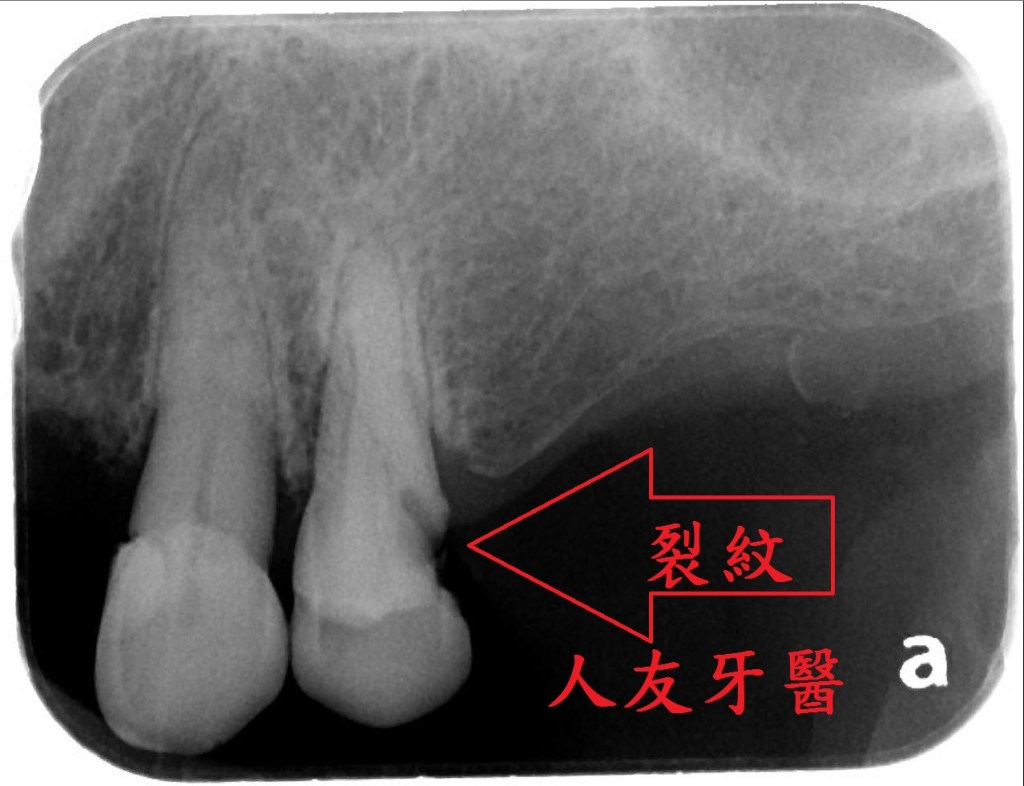

想詢問周醫師如何處理。醫師看了X-RAY發現右邊側門牙紅色圓圈的地方有病變,有可能留不住。左邊側門牙藍色箭頭牙齒有裂到肉,也可能留不住。經過討論後建議都拔除。